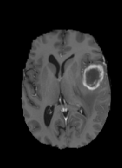

The dataset’s MR images are preprocessed so that the skulls and neck regions are removed. The images are aligned and co-registered to correct any head tilt or mismatches between MR modalities. Each voxel in the image corresponds to of brain tissue. Figure 5 illustrates a 2D axial input MR Images sample and the corresponding ground truth. The input images (a-c) show the different MR modalities: FLAIR, T1CE, and T2 images. The ground truth consists of peritumoral edema (ED) marked in light grey given by an intensity value of , enhancing tumor (ET) represented as a white region with as an intensity value, and the non-enhancing tumor (NET) and necrotic core region (NCR) as dark grey with an intensity value of . The models are evaluated as enhancing tumor (ET), tumor core (TC), and whole tumor (WT). The tumor core corresponds to NET/NCR and the enhancing tumor region. The whole tumor corresponds to all three tumor regions put together. The research aims to learn the ED, NET/NCR, and ET regions.